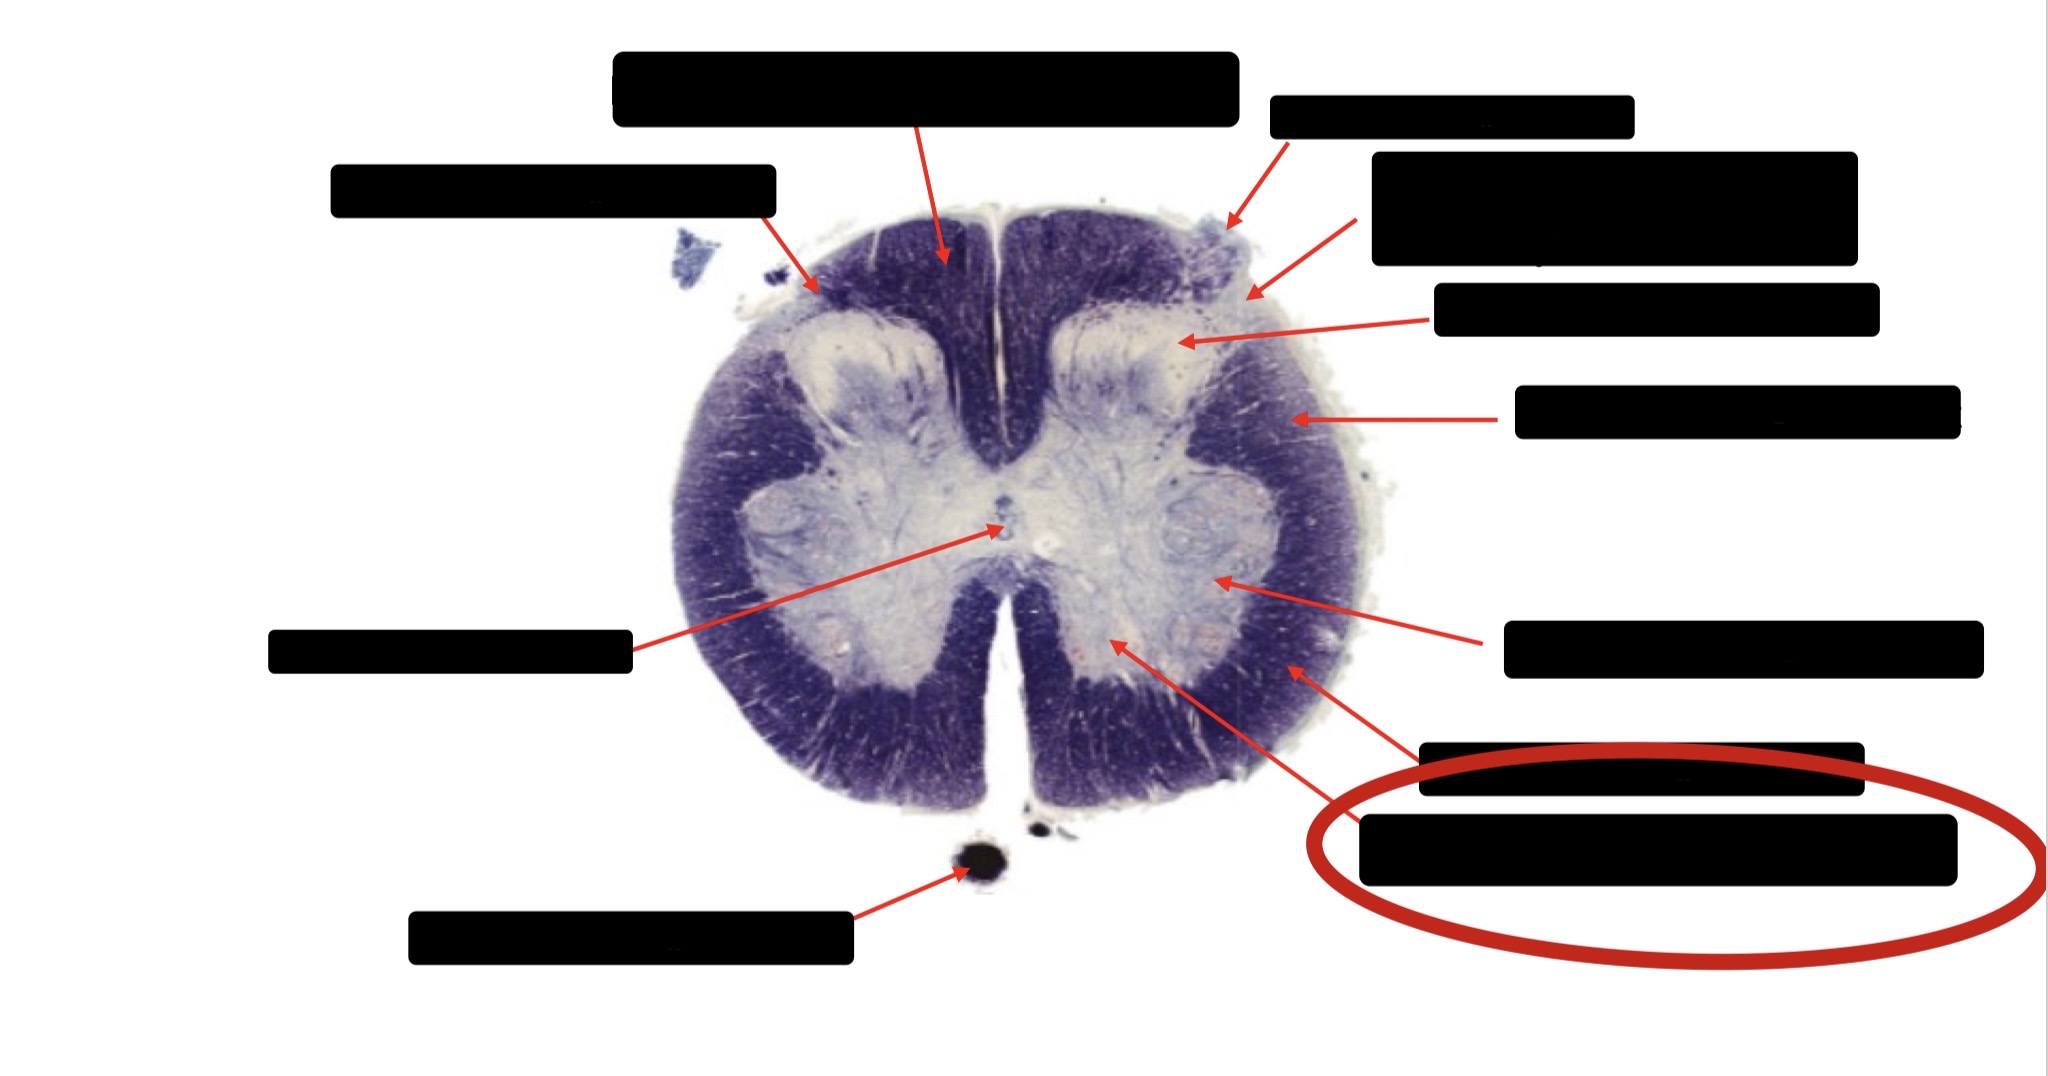

Spinothalmic Tract

Central Canal

Posterior Column (Fasciculus Gracilis)

Large Fiber Entry Zone

Lissaeur’s Tract & Small Fiber Entry Zone

Substantia Gelatinosa

Lateral Corticospinal Tract

Ventral Root Fibers

Anterior Horn Motor Neurons

Anterior Medial Fissure

Dorsal Rootlet

Posterior Spinocerebellar Tract

Anterior Spinocerebellar Tract

Posterior Column (Fasciculus Cuneatus)

Anterior Horn Motor Neurons (Distal Muscles)

Anterior Horn Motor Neurons (Proximal Muscles)